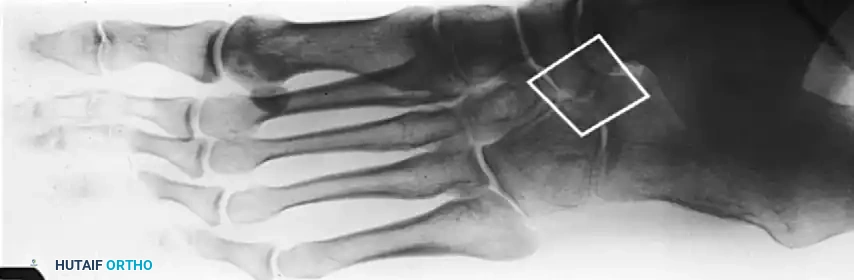

FIGURE 82-76 A: Congenital talonavicular tarsal coalition (Anteroposterior view).

FIGURE 82-76 B: Congenital talonavicular tarsal coalition (Lateral view).

FIGURE 82-76 C: Congenital talonavicular tarsal coalition (Oblique view).